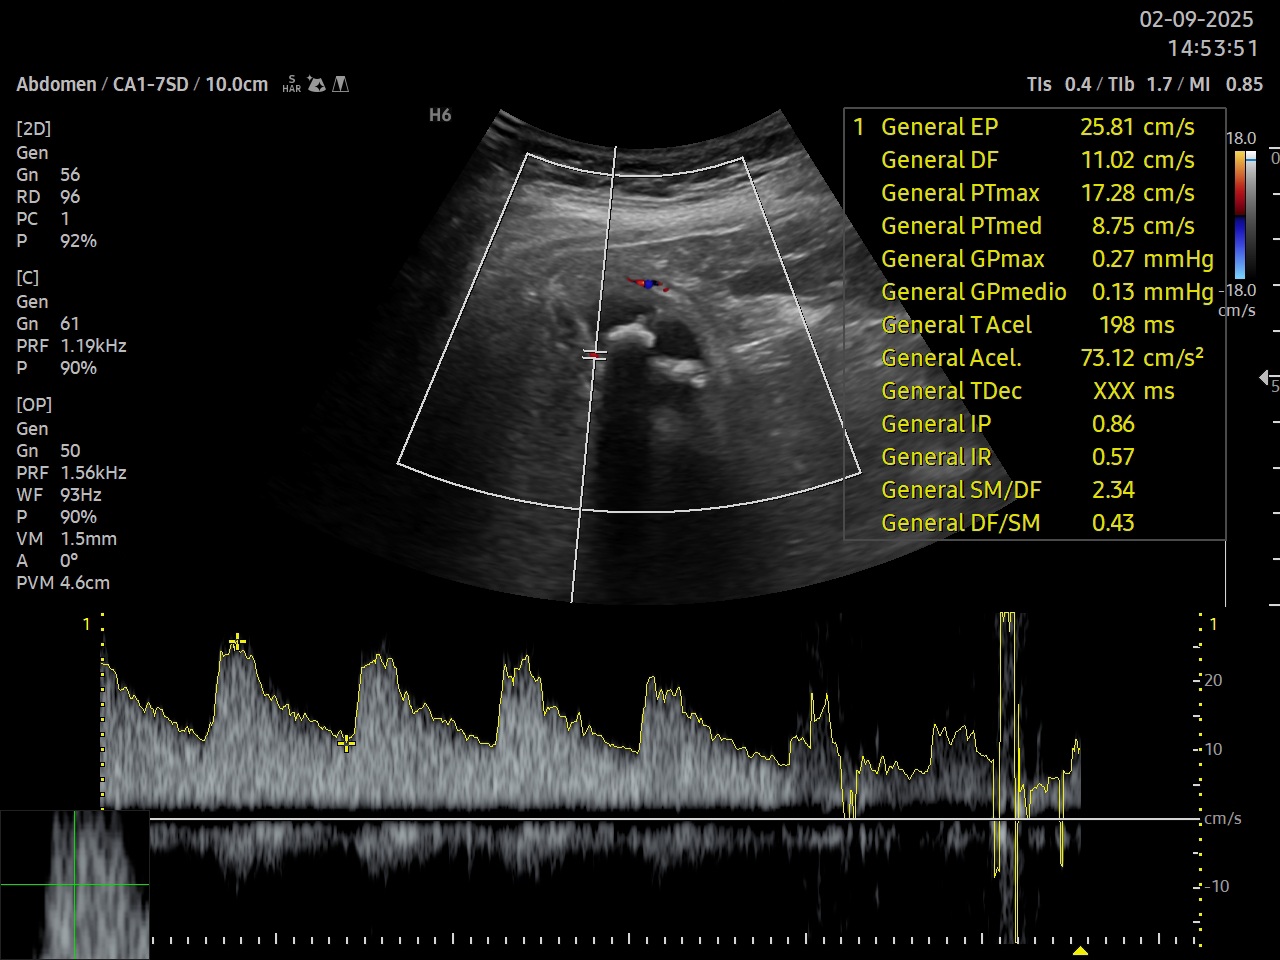

Ecografía clínica: parénquima hepático homogéneo de bordes lisos, signo de Murphy ecográfico positivo, vesícula biliar distendida a pesar de no ayuno con tres imágenes hiperecogénicas con centelleo y sombra posterior, pared engrosada hiperecogénica, se detecta líquido perivesicular. Doppler pulsado a nivel de arteria cística. Páncreas visible en parte sin alteraciones en su interior, no se visualiza Wirsung ni dilatación a nivel de ampolla de Vater, bazo y riñones de tamaño y ecoestructura normal, mioma uterino, vejiga parcialmente replecionada, aorta de calibre normal.

Según los criterios de Tokio 2018, el diagnóstico de colecistitis se establece con la combinación de signos locales de inflamación: dolor en hipocondrio derecho y Murphy positivo, signos sistémicos de inflamación: leucocitosis con neutrofilia, hallazgos de imagen: pared vesicular engrosada (mas de 3 mm), vesícula distendida, presencia de litiasis y Murphy ecográfico positivo, líquido pericístico así como elevación de la velocidad pico sistólica en la arteria cística.